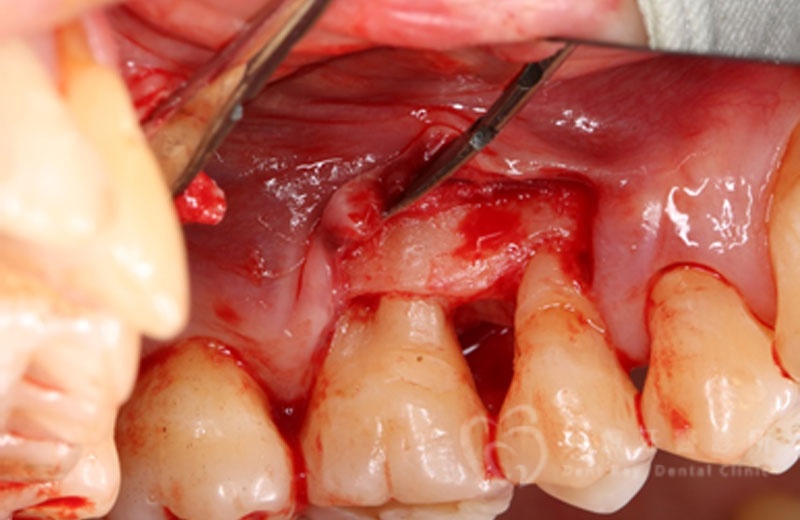

牙周手術案例三

術後六個月